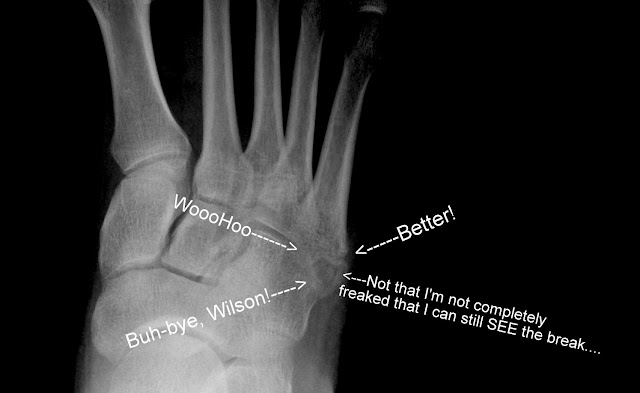

And as I said, the news… well, it just wasn’t good…

The news was freaking grrrrrrreat! Great news!

I think the mental road back to running is going to be just as tough as the physical. Afterall, I can still see the boo-boo on the x-rays. The doc said that I may be able to see it years from now.